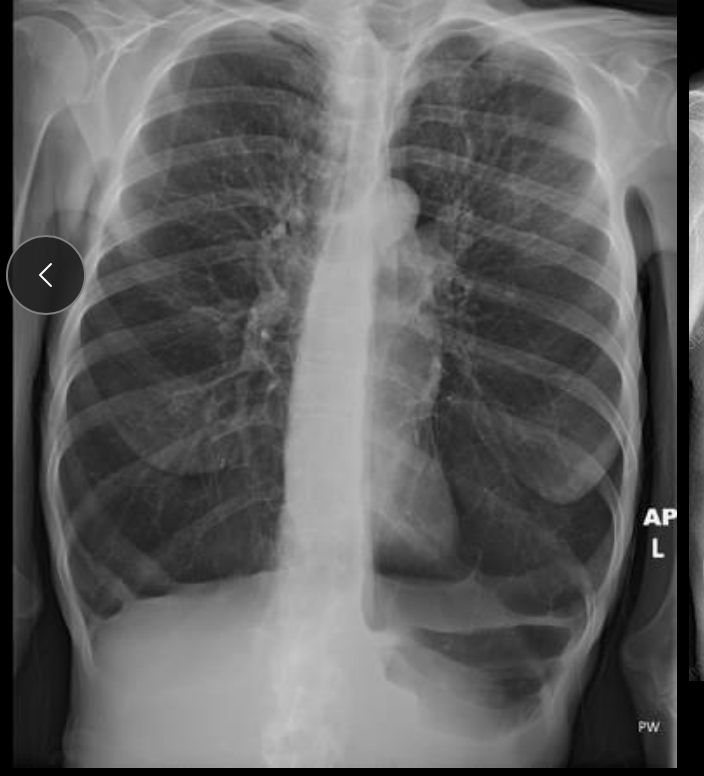

Aplanamiento del diafragma

Disfunción marcas broncovasculares

Hiperlucidez pulmonar

Corazón en gota

Rx enfisema